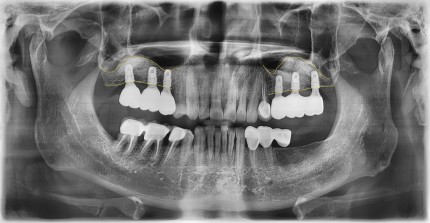

임플란트를 식립할 공간이 부족할 땐?쿨쿨플란트치과 상악동 골이식 임플란트

상악동 골이식 임플란트, 아무데서나 받지마세요!

쿨쿨플란트치과 상악동 골이식 임플란트 과정

쿨쿨플란트치과 상악동골이식 치료 전후사진